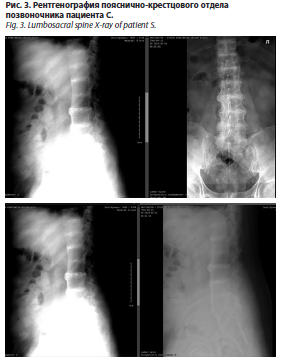

На рентгенограммах пояснично-крестцового отдела позвоночника в прямой и боковой проекциях (рис. 3) травматических изменений не выявлено. Физиологический лордоз сглажен. Ось отдела незначительно отклонена влево. Межпозвонковые пространства снижены, кортикальные пластинки тел позвонков склерозированы, утолщены, определяются зоны уплотнения от межпозвонковых пространств (кальцификация?). Тела позвонков равномерные по высоте. По передним и боковым краям тел позвонков – краевые остеофиты. Определяются сужение суставных щелей дугоотростчатых суставов, склероз субхондральных отделов. Заключение: рентгенологическая картина дегенеративно-дистрофических изменений грудного отдела позвоночника. Спондилез. Сколиоз. Спондилоартроз. Хондрокальциноз?

На рентгенограммах грудного отдела позвоночника в прямой и боковой проекциях (рис. 2) травматических изменений не выявлено. Физиологический грудной кифоз сохранен. Ось отдела отклонена вправо (угол сколиоза 7° по Коббу на вершине ThVIII). Межпозвонковые пространства снижены, кортикальные пластинки тел позвонков склерозированы, утолщены, определяются зоны уплотнения от межпозвонковых пространств (кальцификация?). Тела позвонков равномерные по высоте (на высоте кифоза определяется снижение высоты тел позвонков в передних отелах, больше данных, свидетельствующих о дистрофических изменениях). По передним и боковым краям тел позвонков – краевые остеофиты. Определяются сужение суставных щелей дугоотростчатых суставов, склероз субхондральных отделов. Заключение: рентгенологическая картина дегенеративно-дистрофических изменений грудного отдела позвоночника. Спондилез. Сколиоз. Спондилоартроз. Хондрокальциноз?На рентгенограммах пояснично-крестцового отдела позвоночника в прямой и боковой проекциях (рис. 3) травматических изменений не выявлено. Физиологический лордоз сглажен. Ось отдела незначительно отклонена влево. Межпозвонковые пространства снижены, кортикальные пластинки тел позвонков склерозированы, утолщены, определяются зоны уплотнения от межпозвонковых пространств (кальцификация?). Тела позвонков равномерные по высоте. По передним и боковым краям тел позвонков – краевые остеофиты. Определяются сужение суставных щелей дугоотростчатых суставов, склероз субхондральных отделов. Заключение: рентгенологическая картина дегенеративно-дистрофических изменений грудного отдела позвоночника. Спондилез. Сколиоз. Спондилоартроз. Хондрокальциноз?